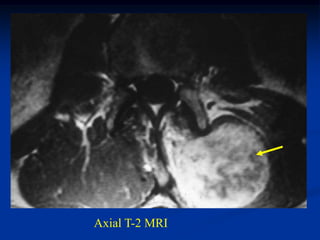

Axial T-2 MRI

Another axial T-2 MRI showing cystic fluid-fluid levels